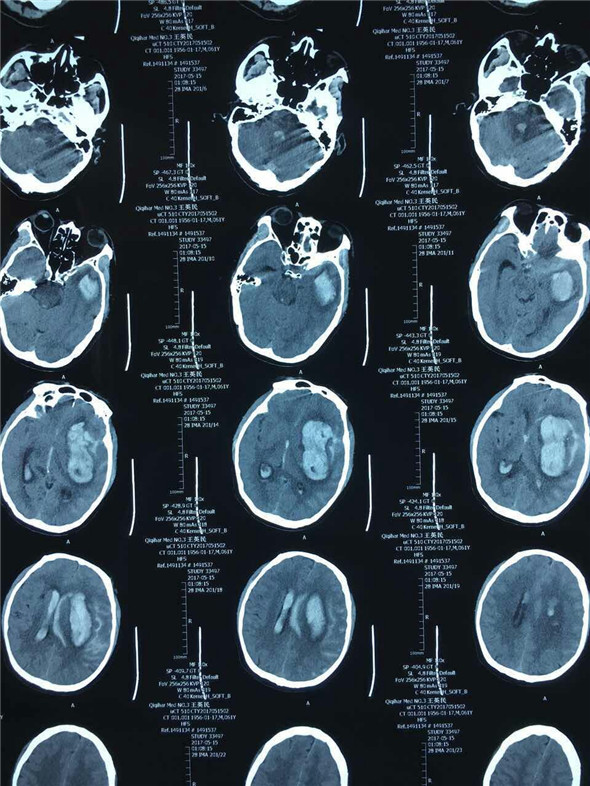

患者王先生因头痛4小时入住神经内二科,完善相关检查给予对症治疗过程中患者出现意识不清,急诊行头CT示蛛网膜下腔出血、颅内大面积出血,并且患者意识不清逐渐加重,双侧瞳孔不等大,已出现脑疝,情况十分危险。对于这位危重症患者来说时间就是生命,神经内二科赵宏主任立即联系神经外二科吴卫东主任紧急会诊。

因术前缺少脑256CT及全脑血管选择性造影,动脉瘤的位置、大小情况无从知晓,所以手术切口的设计,术中可能发生的情况的预判,对手术能否成功有着至关重要影响。术中吴主任凭借多年的手术经验及娴熟的手术技巧,仔细而充分的清除颅内血肿,在左侧大脑中动脉M1、M2交界处暴露出动脉瘤,最大直径约1.8cm,2枚动脉瘤夹成功夹闭。经过3个小时紧张而有序的手术,王先生的手术顺利完成。术中将骨瓣成功复位,避免了二次手术,减轻了患者的经济负担,术毕患者双侧瞳孔回复正常,术后第一日患者清醒。

术前头部CT